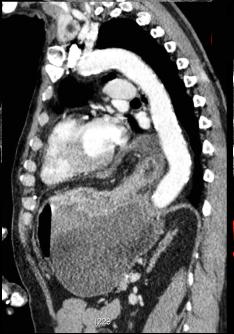

Hernie hiatale par roulement

avecvolvulus gastrique de type mesenterico-axiale du

segment hernie du corps gastrique . Image

radiologique TDM en coupe sagitale . |